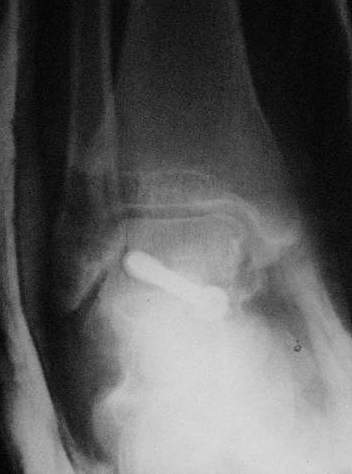

Переломовывих тарана с повреждением медиальной стороны. Через 4 часа после поступления проведена репозиция и фиксация тарана после Irrigation&Debridment. Частичное несращение медиальной лодыжки не беспокоит, вернулся к активному образу жизни. Полная нагрузка разрешена через 11 недель. Финальные снимки через 11 месяцев.